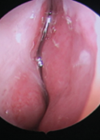

Endoscopic arytenoid abduction lateropexy for bilateral vocal cord paralysis in neonates

We are delighted to publish a further update on the use of the technique for vocal fold lateralisation in neonates from Laszlo Rovo and Shahram Madani, who have previously informed us of this new technique [1]. These cases are rare...